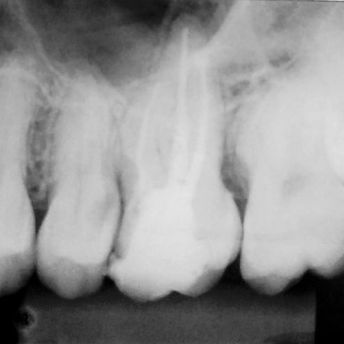

TRATAMENTO E RETRATAMENTO ENDODÔNTICO

Câmera Intraoral;

Rx portatil;

Sensor rx;